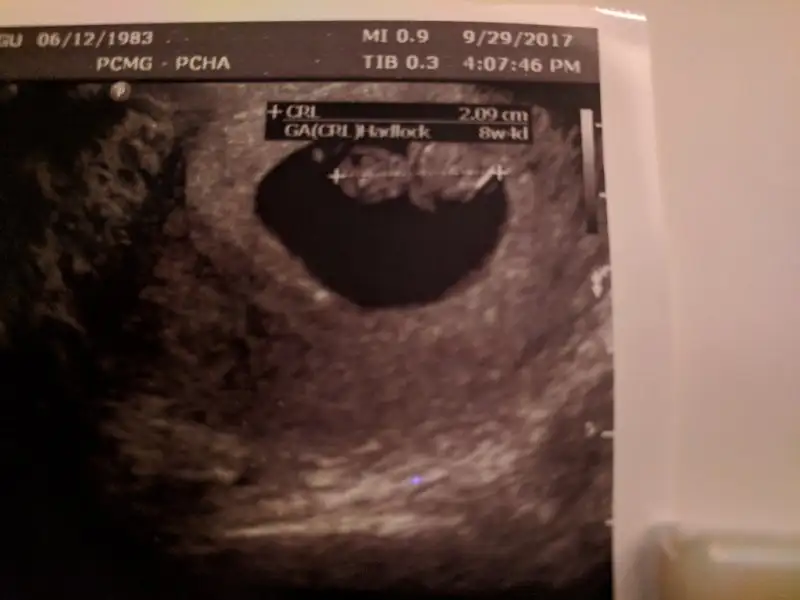

Sevinclihayat Sevinclihayat randevum iyi gecti. Bu benim bebişim ve kollari. Kalbi 175 ti erkek sanırım.

Eklentiler

• tmp_23963-IMG_20170929_225108-1024x7683569176480134817382.webp

tmp_23963-IMG_20170929_225108-1024x7683569176480134817382.webp

13,6 KB · Görüntüleme: 89